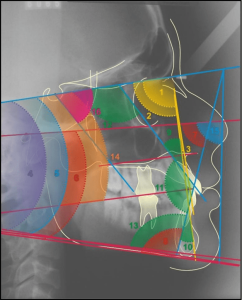

Thus, a new planning for rehabilitation was executed, having as a starting point the facial molding. The clinical sequence used was: skin cleansing by removing makeup and oiliness, protection of hair with bandage, application of solid vaseline in the facial hairs, tamponade of the nostols with cotton wool and a canudo for mouth breathing (figure 25). Then, the alginate (Jeltrate Dustless®, Dentsply, Argentina) was started using two parts, with the proportion of water/powder being 4:4. After being manipulated, it was deposited in small parts in the region to be molded with the aid of a spatula (figure 26), then the retention with cotton on the alginate was performed and the common plaster type II (Asfer®, Brazil) was added, in order to confer stiffness (figure 27), preventing deformation during its removal.

Figure 25: Preparation for the beginning of facial molding.

Figure 26: Alginate deposition on the face.

Figure 27: Insertion of plaster on the retention.

The mold was removed with slight movements, prompting the patient to move the mime muscles (figure 28). Immediately after molding, the mold was filled with type IV plaster (Durone®, Dentsply, Argentina) to obtain the facial model. With the aid of a vibrator, the plaster was deposited on the mold to prevent the formation of bubbles and when taking prey, the model was removed, so the finishes were executed (figure 29). Subsequent surgical removals, the treatment plan of choice was radiotherapy, being performed for two months, where it has already begun and is under medical follow-up.

Figure 28: Mold removed.

Figure 29: Model of the finished face.

Through histopathological examinations of the last surgeries performed on the patient, which indicated margin compromise, a more invasive surgery was planned by her physicians, which may compromise noble structures of facial support. Thus, facial molding was proposed, being as a guide for possible aesthetic-functional rehabilitation, after inavasive surgical procedure. The materials described in the literature for the preparation of facial molding are elastomers, hydrocolloides and plasters (AQUINO et al., 2012). The chosen technique is quite usual, low cost and easy execution, the material of choice for the case was irreversible hydrocolloside and plaster. Alsiyabi and Minsley (2006) mention that the conventional technique using irreversible hydrocolloide can result in inaccuracy and distortion of molding. Then, the authors propose the use of silicone, which will reduce clinical clothing and the fact that the material presents dimensional stability, deformation resistance and high tear resistance. On the other hand, the main disadvantage is the high cost of the material. Thus, facial molding performed with irreversible hydrocolloide proved to be effective, without distortions and low cost.